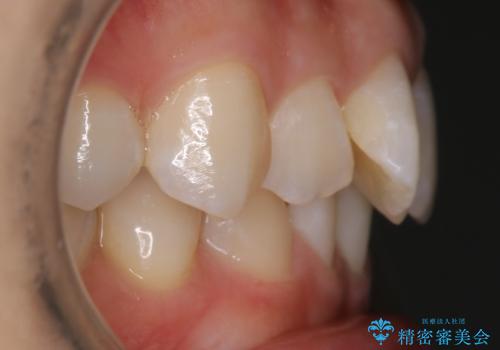

- 前歯のガタつきを主訴に来院されました。

生まれつき下の前歯が1本少なく、その分のスペースを上の前歯がガタつくことで埋めているという状況でした。

上下それぞれのガタつきをとっていく過程で、歯1本分のスペースの差を、上顎の前歯のIPRで調整して並べる方法をご提案させていただきました。

こういったケースの治療では欠損している歯の本数分反対の顎の歯(上顎に欠損がある場合は下顎の歯)を抜歯してスペースの調整をする場合や、欠損歯の幅分のIPRを反対の顎の歯に設定することでスペースのコントロールをするという方法、欠損している歯の分のスペースを残して矯正を終了し最後にブリッジ治療やインプラントで歯の本数を増やすという方法があり、状況や患者さんの希望により選択をしていきます。